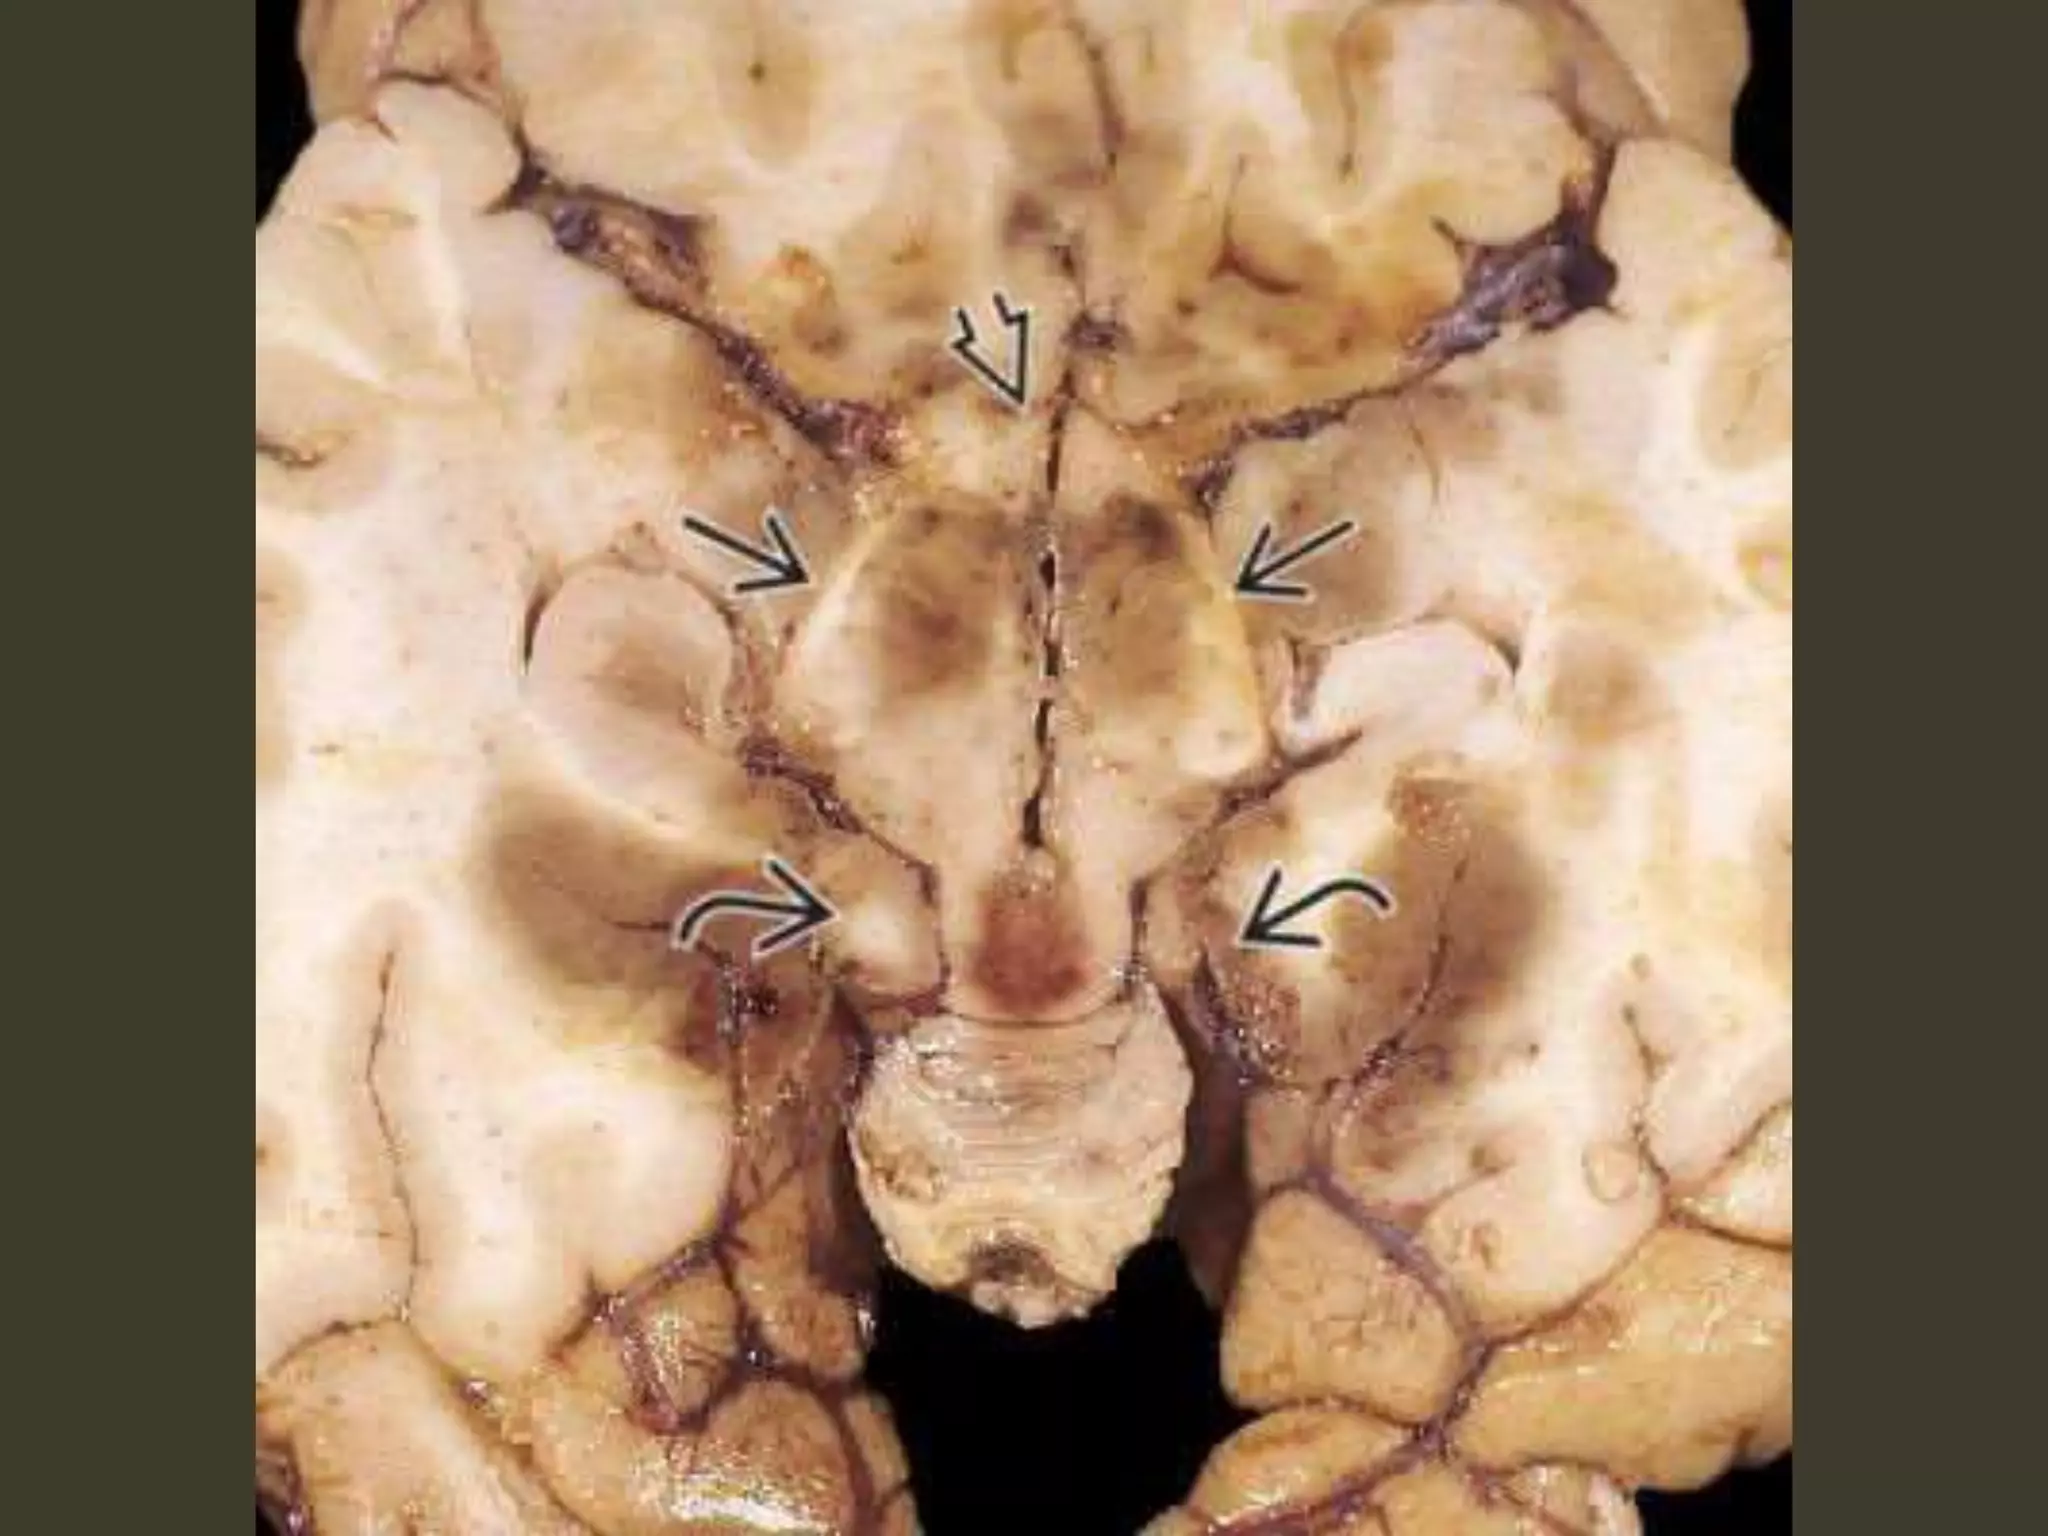

Complete bilateral DTH

both temporal lobes herniate medially into the

tentorial hiatus

midbrain and pons displaced inferiorly through

the tentorial incisura

The angle between the midbrain and pons

is progressively reduced from 90° to almost 0°

Duret hemorrhage

"Top-down" mass effect displaces the midbrain

inferiorly

closes the midbrain-pontine angle

Perforating arteries from basilar artery

are compressed and buckled

hypothalamic and basal

ganglia infarcts

perforating arteries from the

circle of Willis compression against the

central skull base

hypothalamic and basal ganglia

infarcts